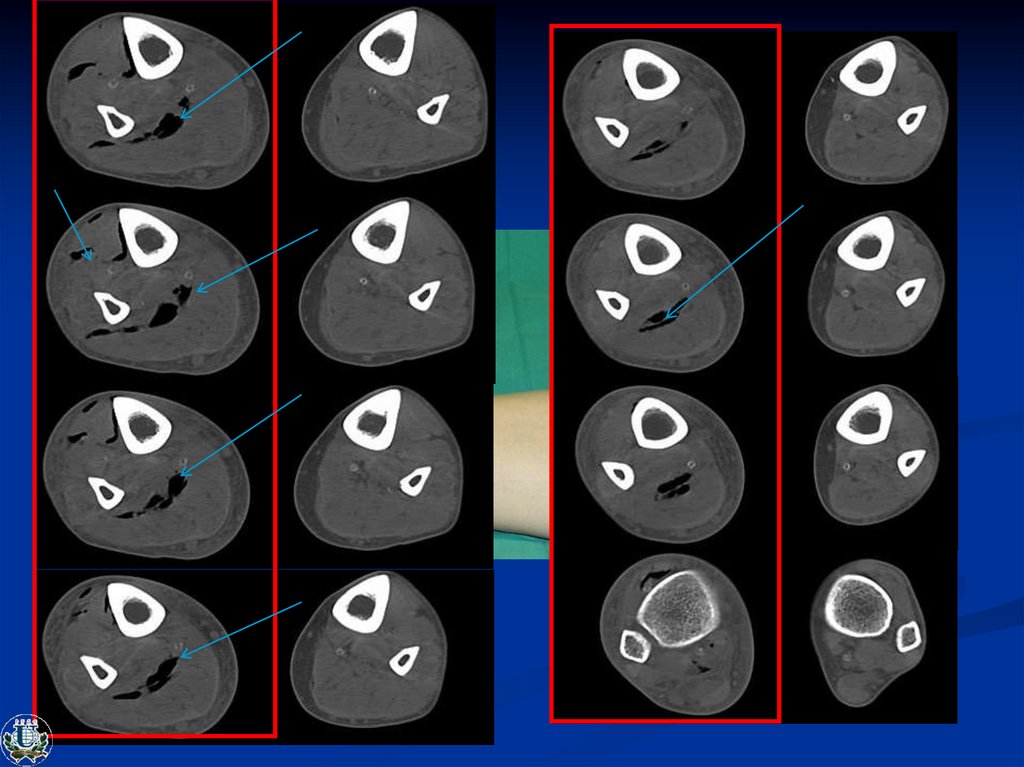

Пациент С., 51 год. Диагноз: СД 2 тип. СДС, нейропатическая форма. Влажная гангрена

4-го пальца, флегмона правой стопы с влажным некрозом среднего отдела стопы.